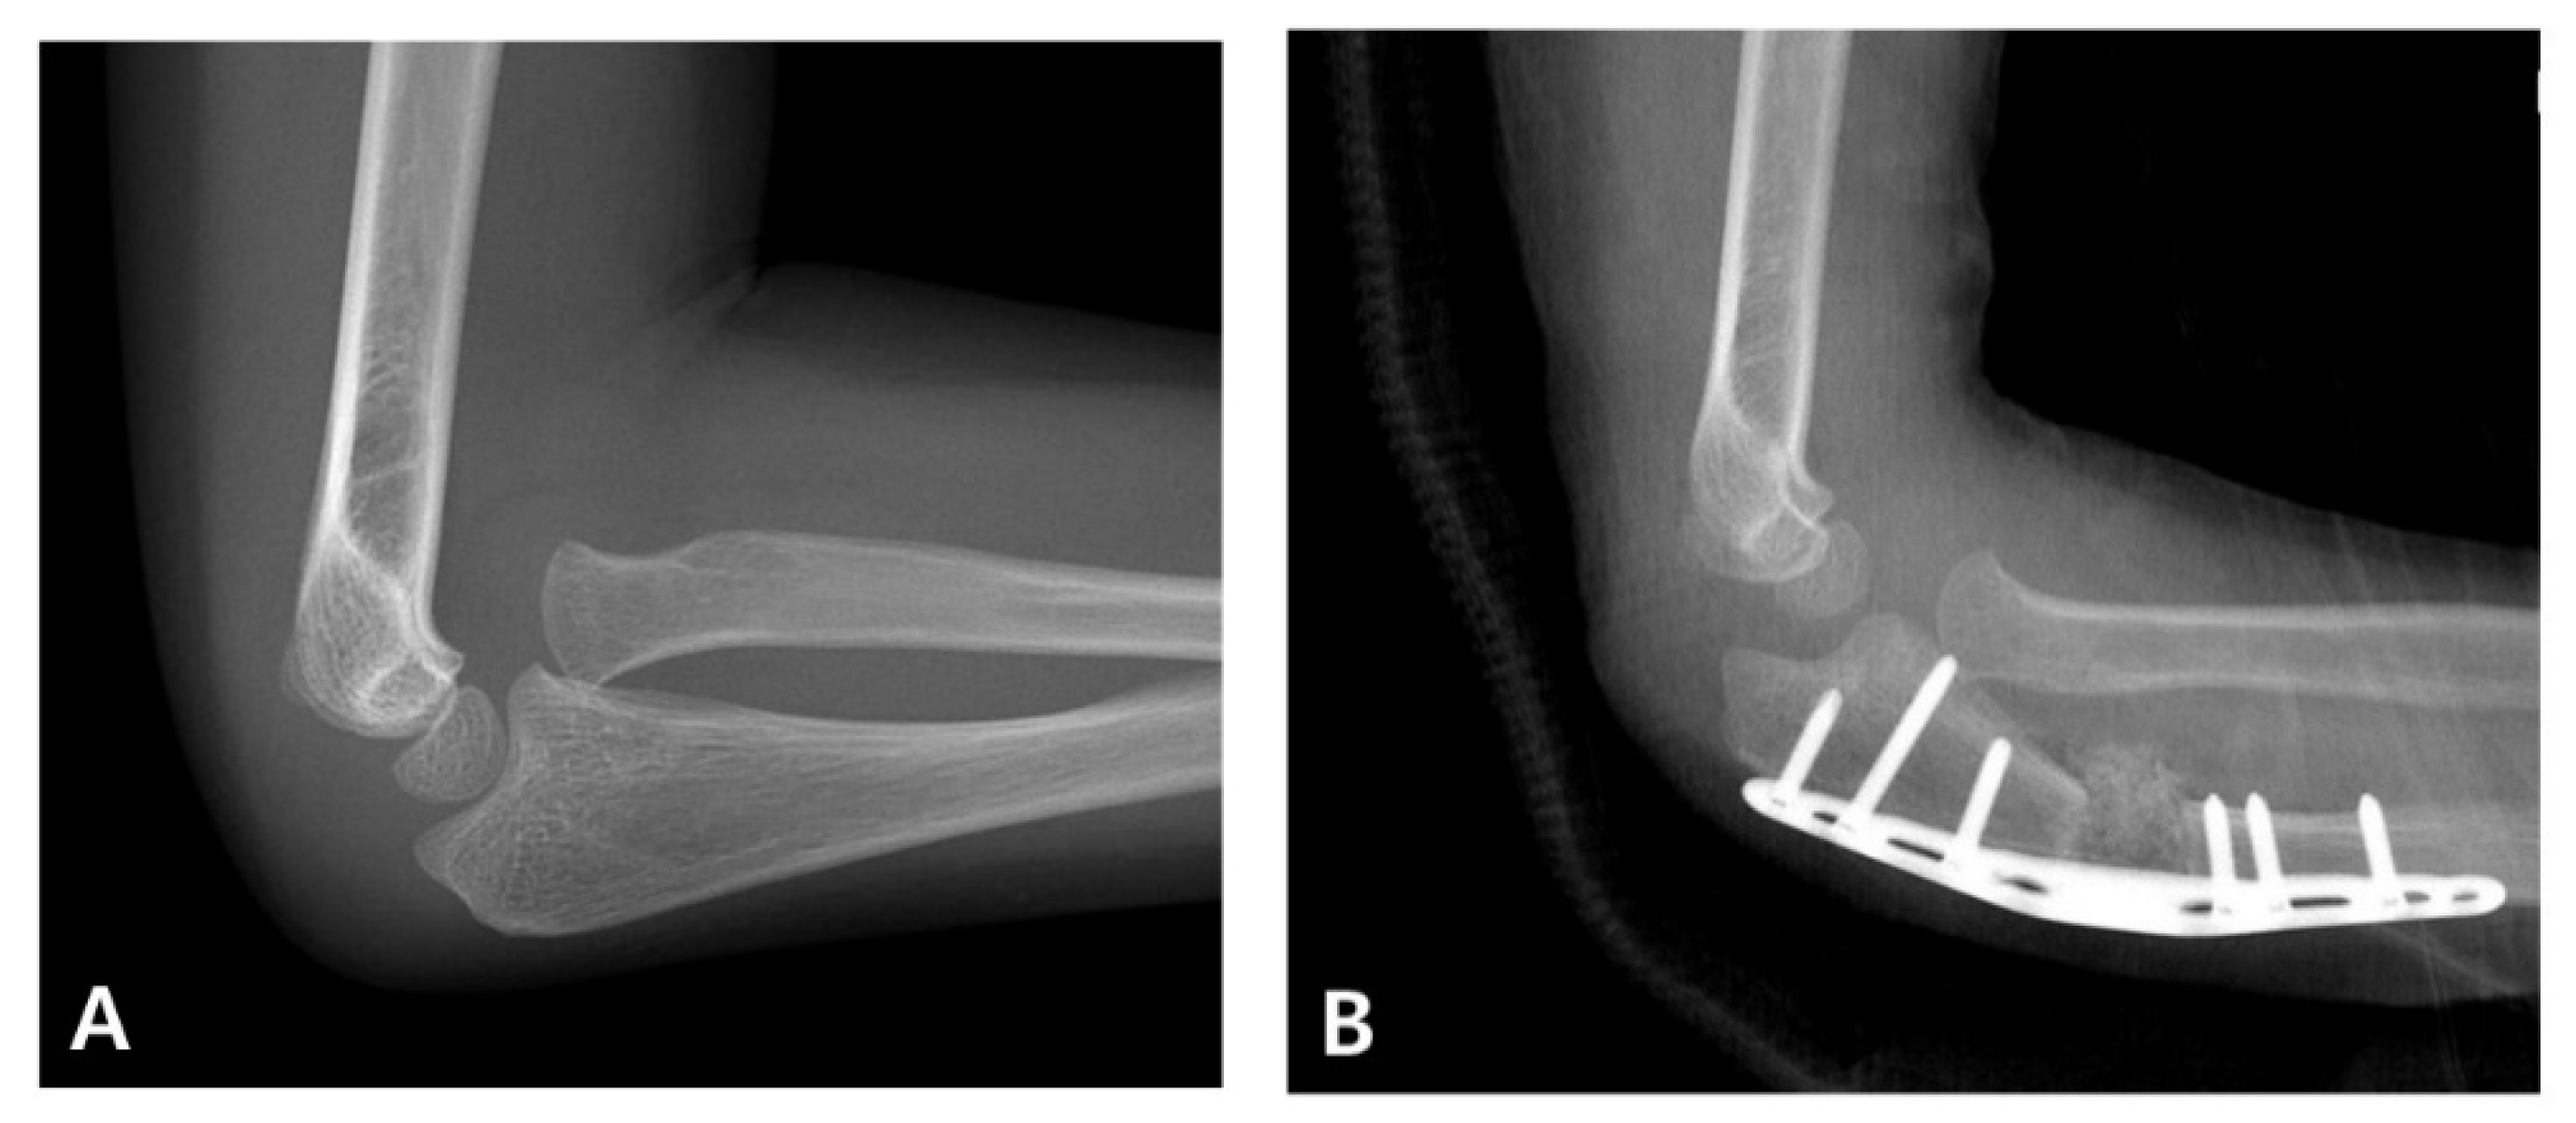

Management in children initially involves the urgent anatomical realignment of the ulna and a reduction in the radial head. This is most commonly achieved through closed reduction and casting as a first-line conservative approach. If successful, this method stabilizes the radiocapitellar joint and restores elbow function without requiring surgical intervention (Figure 1) [4]. However, in cases in which the alignment is unstable or cannot be maintained, surgical stabilization using techniques such as intramedullary nailing or plating is indicated [5,6]. Therefore, a prompt and accurate diagnosis is critical for determining the appropriate treatment pathway and avoiding long-term complications, such as persistent radial head dislocation, limited motion, and elbow deformity.

Figure 1. Radiographic progression of an acute pediatric Monteggia fracture treated conservatively. (A) Initial anteroposterior and lateral elbow radiographs of a 3-year-old boy revealing anterior dislocation of the radial head with a fracture of the proximal ulna, consistent with a Bado type I Monteggia fracture. (B) Closed reduction and casting were performed promptly. Post-reduction images confirmed the anatomical realignment of both the ulna and radial head. (C) Follow-up radiographs obtained 2 months after the injury demonstrate maintained reduction and progressive healing without the need for surgical intervention.